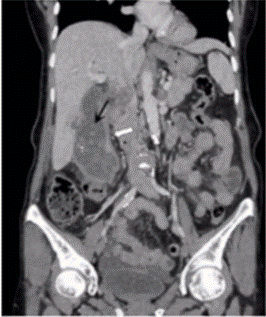

A 3-year-old boy presents with fever and cough. A chest x-ray was done, which showed the following findings. Which of the following is the most likely underlying pathology?

Options:

A) Right upper lobe collapse

B) Right upper lobe abscess

C) Right upper lobe consolidation

D) Bronchogenic carcinoma

Correct answer: C) Right lobe consolidation